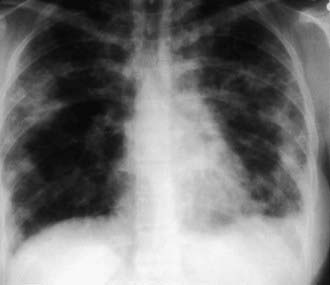

The presence of microfilariae in the body has no apparent pathologic consequences except in persons with tropical pulmonary eosinophilia, a syndrome of filarial etiology in which microfilariae are found in the lungs and lymph nodes but not the bloodstream. It occurs only in individuals who have lived for years in endemic areas. Men 20-30 yr of age are most likely to be affected, although the syndrome occasionally occurs in children. The presentation includes paroxysmal nocturnal cough with dyspnea, fever, weight loss, and fatigue. Rales and rhonchi are found on auscultation of the chest. The x-ray findings may occasionally be normal, but increased bronchovascular markings, discrete opacities in the middle and basal regions of the lung, or diffuse miliary lesions are usually present (Fig. 288-1). Recurrent episodes may result in interstitial fibrosis and chronic respiratory insufficiency in untreated individuals. Hepatosplenomegaly and generalized lymphadenopathy are often seen in children. The diagnosis is suggested by residence in a filarial endemic area, eosinophilia (>2,000/µL), compatible clinical symptoms, increased serum IgE (>1,000 IU/mL), and high titers of antimicrofilarial antibodies in the absence of microfilaremia. Although microfilariae may be found in sections of lung or lymph node, biopsy of these tissues is unwarranted in most situations. The clinical response to diethylcarbamazine (2 mg/kg/dose tid PO for 12-21 days) is the final criterion for diagnosis; the majority of patients improve with this therapy. If symptoms recur, a 2nd course of the anthelmintic should be administered. Patients with chronic symptoms are less likely to show improvement than those who have been ill for a short time.

Figure 288-1 Chest radiograph of a woman with tropical pulmonary eosinophilia. Reticulondular opacities are scattered throughout both lungs.

(From Mandell GL, Bennett JE, Dolin R, editors: Principles and practice of infectious diseases, vol 2, ed 6, Philadelphia, 2006, Elsevier, p 3274.)